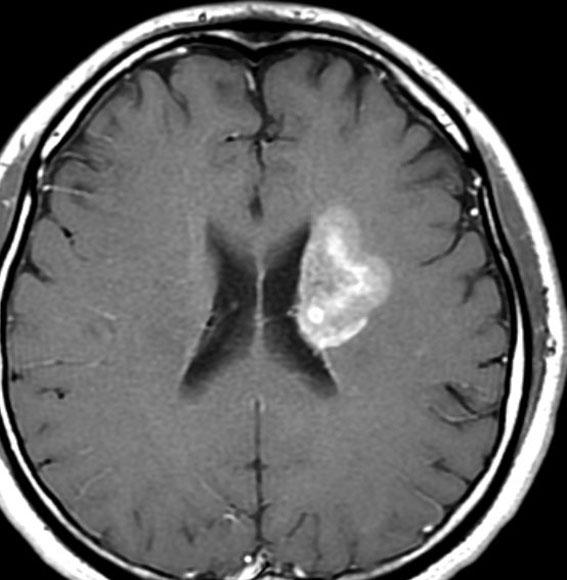

放射線治療後9週目

フレア画像です。たった2週間で脳浮腫が高度の脳浮腫となっています。失語症と右片麻痺と認知機能低下が生じました。ステロイド剤とグリセリンの点滴を行いました。

放射線治療13週目

右はガドリニウム増強です。ステロイドとグリセオールの点滴では制御できませんでした。悪性神経膠腫の病名で保険適応があるアバスチン(ベバシズマブ 10mg / kg)の投与を開始しました。